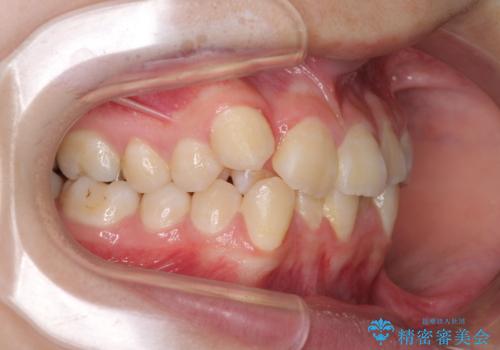

八重歯で正中が右にずれている ワイヤー装置での抜歯矯正で正中位置を改善

右上の八重歯が特に著しく、上顎正中が右側にシフトしていました。

デコボコが強いため小臼歯4本を抜歯し、上顎正中を左側に移動させるために補助装置を使用して、ワイヤー装置にて矯正治療を行うこととしました。

正中位置の改善に時間がかかることが予想され、2年半を治療期間の目標としておりましたが、20歳と年齢が若いこともあり、2年2ヶ月で治療を終えることができました。